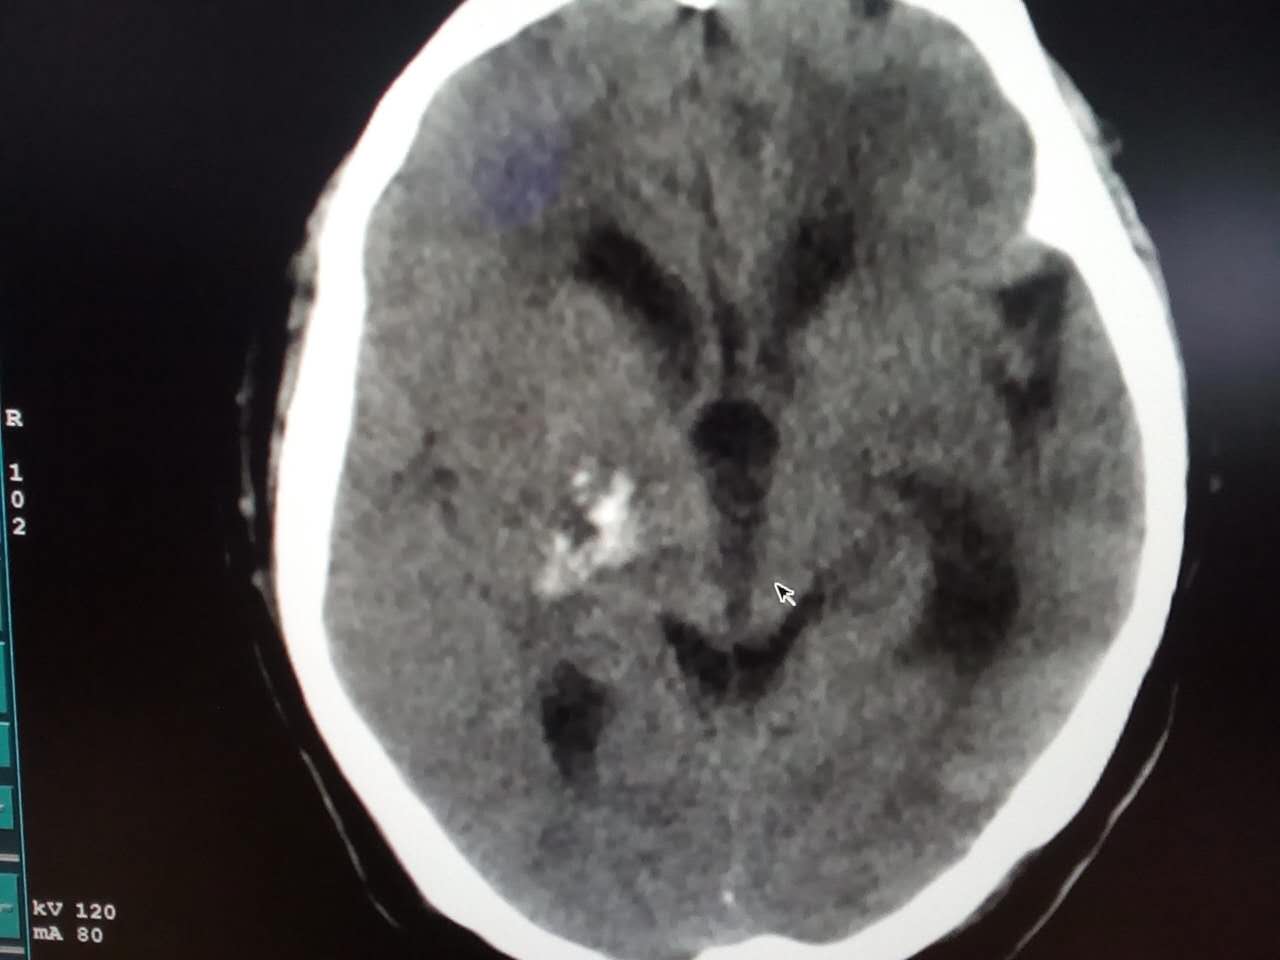

CT52398:请会诊,病人,女,66岁。

病人现在昏迷,既往患过脑梗、脑出血。

相当右侧颞顶叶可见不规则团块状混杂密度区,内见斑片斑点及扭曲条状钙化及似脑脊液小片状低密度影。其间夹杂少许等密度影,团块无明显占位效应。两侧侧脑室前角、基底节区、左侧辐射冠区见斑片状似脑脊液密度。脑室扩大。考虑:右侧颞顶叶动静脉畸形。两侧侧脑室前角、基底节区、左侧辐射冠区多发性腔梗,部分软化灶。脑萎缩。

1、右侧动静脉畸形伴钙化可能。

2、多发腔梗 脑白质脱髓鞘改变 脑萎缩伴左侧顶叶软化灶。

支持动静脉畸形(AVM)伴钙化。

脑白质脱髓鞘改变。

右侧半卵圆中心AVM伴多发钙化灶形成

左侧顶叶脑软化灶\多发腔隙性脑梗塞\脑萎缩

1、右侧AVM伴钙化可能。

2、双侧多发腔梗 脑白质脱髓鞘改变 脑萎缩伴左侧顶叶软化灶。